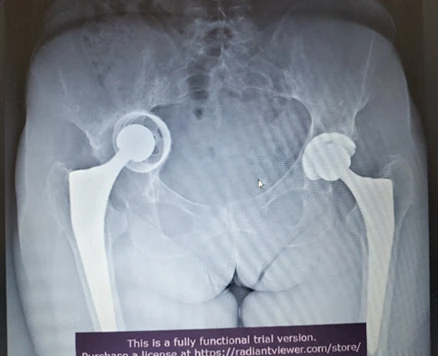

La chirurgia di revisione della protesi d’anca (riprotesizzazione) è un intervento di alta complessità volto a sostituire parzialmente o totalmente un impianto precedentemente inserito che è fallito.

- Mobilizzazione asettica: Scarsa integrazione tra osso e impianto o progressivo allentamento delle componenti senza infezione.

- Usura dei materiali: Il logoramento delle superfici (es. polietilene) può causare osteolisi (distruzione dell’osso circostante) dovuta a una reazione infiammatoria ai detriti da usura.

- Instabilità e lussazione: Spostamento delle componenti che porta alla fuoriuscita della testa femorale dalla coppa acetabolare.

- Qualità e quantità dell’osso: La rimozione del vecchio impianto e l’osteolisi periprotesica spesso causano gravi difetti ossei, rendendo difficile la stabilità primaria del nuovo impianto.

Nella chirurgia di revisione, la ricostruzione dell’osso è la sfida principale. Quando l’osso originario è danneggiato o assente a causa dell’osteolisi, il chirurgo deve ricorrere a tecniche avanzate per ripristinare il supporto meccanico e biologico.

In molti casi è necessario l’utilizzo di protesi speciali (da revisione), innesti ossei o sistemi di ricostruzione modulari per sopperire alla perdita di tessuto.